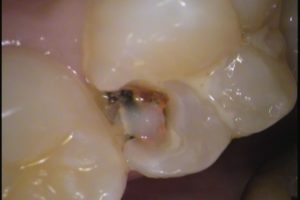

今回の治療は、右上6番目の歯です。

お口の中を見てみると、なにやら黒い所が、、、

場所はわかりますか?

赤丸で囲まれたココです!

デコボコしているのですが、前に治療した形跡があり、

レジンで詰め物がされています。

その周囲から虫歯が入り込み、2次虫歯になってしまっています。

穴をあけてみると

黒い虫歯がでてきました・・・

もう少し掘り進めると、結構黒いですね(^-^;

ちょっと虫歯が大きいです。